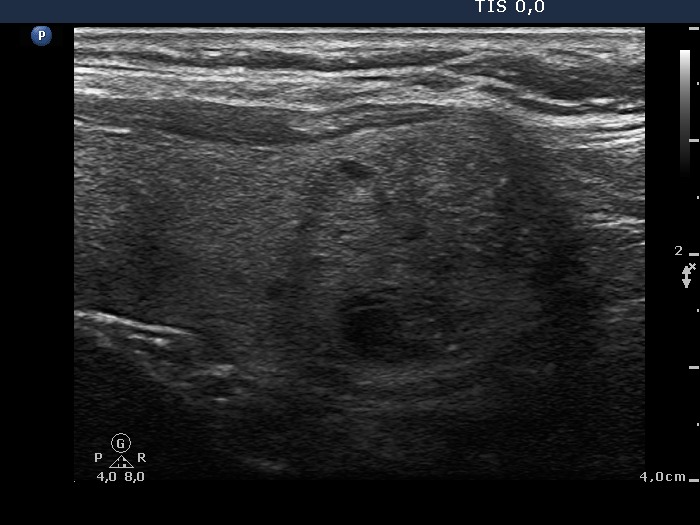

Ultrasonography: The right thyroid contained a moderately hypoechogenic, the left had multiple nodules.

Cytology was performed from the nodule in the right lobe, from the calcified part and from the moderately hypoechogenic nodule in the left lobe. The cytological patterns were identical in all three cases and yielded benign, colloid goiter.

It is worth analyzing the nodule in the right lobe. At first sight it has spiculated margins, however thorough analysis reveals that the irregularity of the margin is caused by the impression of another nodule next to. There is a nodule having macrocalcification. The dorsal part of this lesion seems to be blurred, but this is caused only by the acoustic shadow.